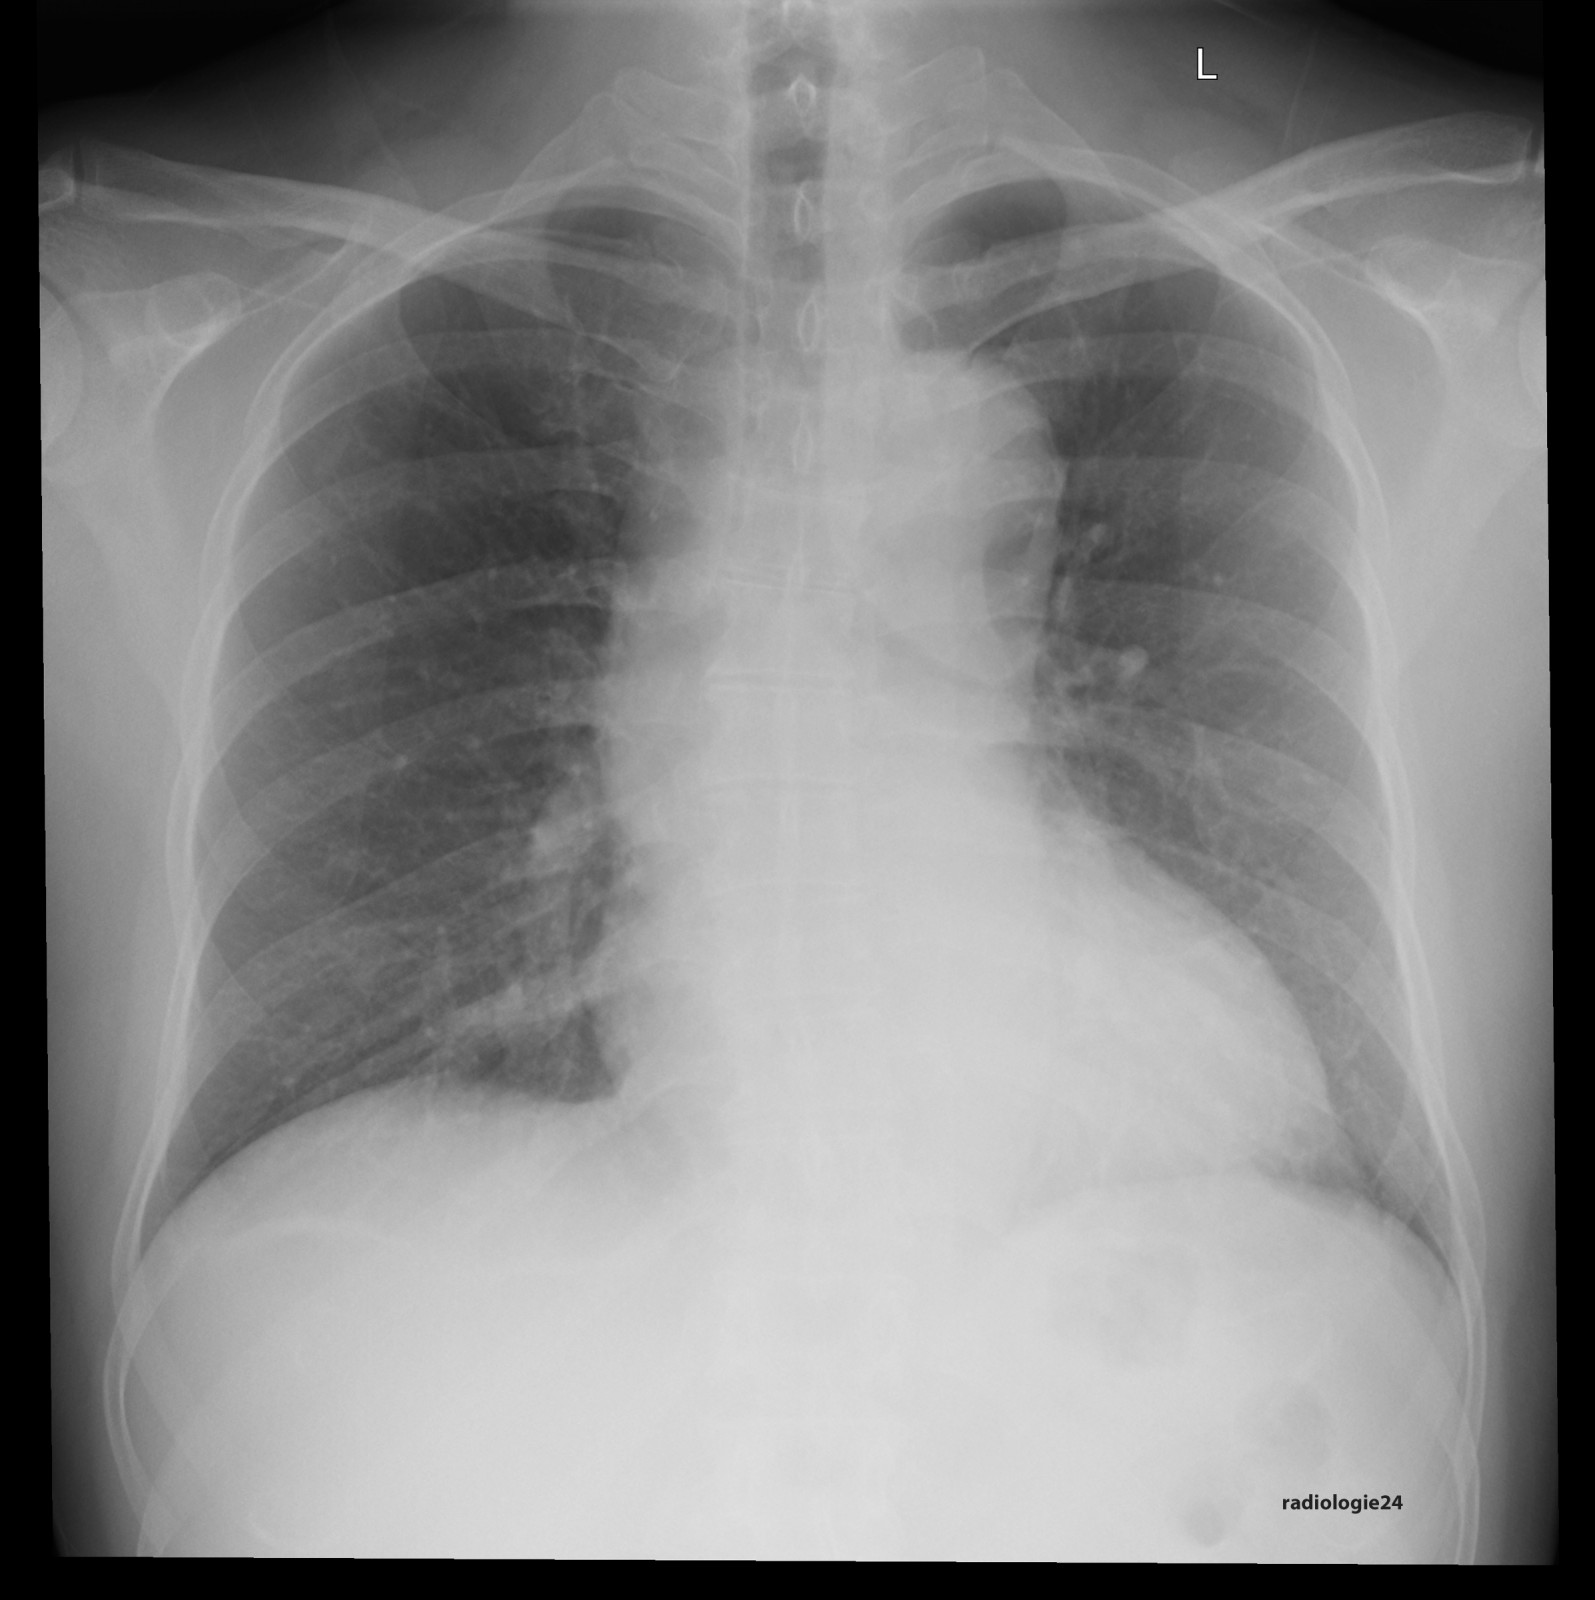

Röntgenfall des Monats Oktober 2017 mit Auflösung

48 jähriger Patient. Klinische Angaben: Thoraxschmerzen, afebril, hypertensiv entgleist. Fragestellung: Infektzeichen? Kardiale Kompensation? Diagnose? Weitere radiologische Diagnostik?

Bild vergrössern

Link zur Auflösung mit ausführlichem Befund

https://www.radiologie24.ch/radiologie-mediathek/roentgenfall_des_monats